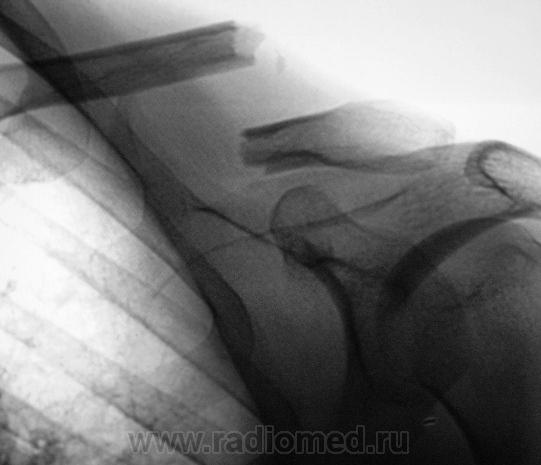

Случай 1

Случай 2.

Случай 3.

Случай 4.

Случай 5.